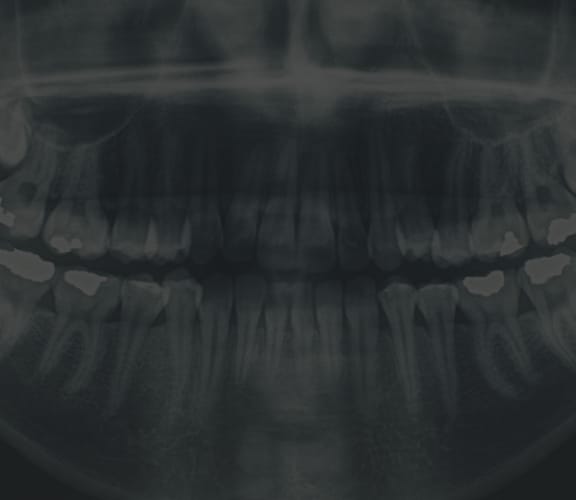

Tooth Extraction

When the extraction of a tooth is required: